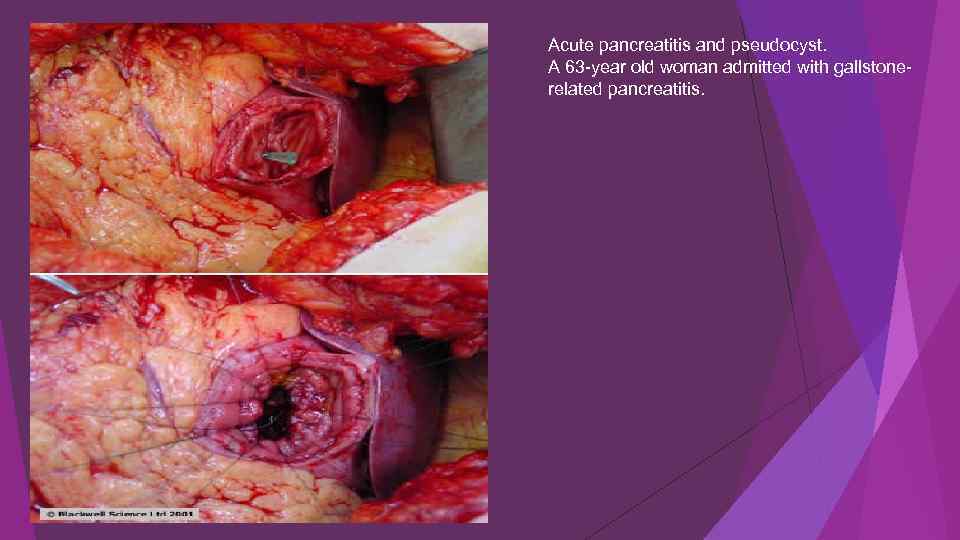

Acute pancreatitis and pseudocyst. A 63 -year old woman admitted with gallstonerelated pancreatitis.

Acute pancreatitis and pseudocyst. A 63 -year old woman admitted with gallstonerelated pancreatitis.